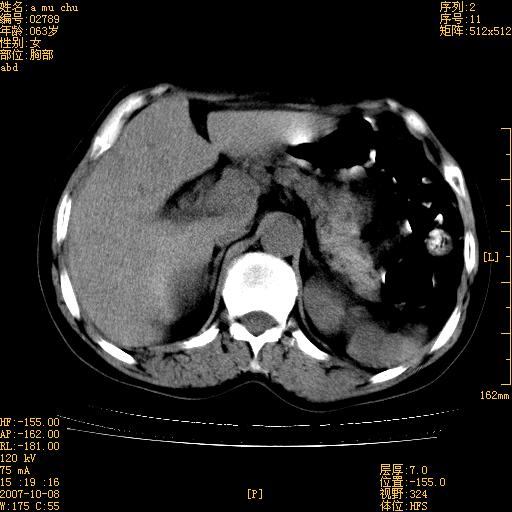

以下是引用王维浦在2007-10-17 21:02:00的发言:[br]胆囊增大,囊壁明显不规则增厚,邻近肝组织浸润,肝内外胆管无扩张。诊断:胆囊ca;[br]胰头软组织肿块影,考虑是由转移肿大的胰后淋巴结、没有肠道准备的十二指肠及胰头共同形成。[br]

以下是引用zhangzexing在2007-10-18 7:13:00的发言:[br]支持胰头占位,慢性胆囊炎. 2.肝左叶前外侧段占位,血管瘤?建议增强

以下是引用影像实习生在2007-10-17 19:49:00的发言:[br]支持胰头占位,慢性胆囊炎. 2.肝左叶前外侧段占位,血管瘤?建议增强.

以下是引用刘振江在2007-10-17 19:42:00的发言:[br]没有增强,胰头癌?胆囊及肝左叶占位?